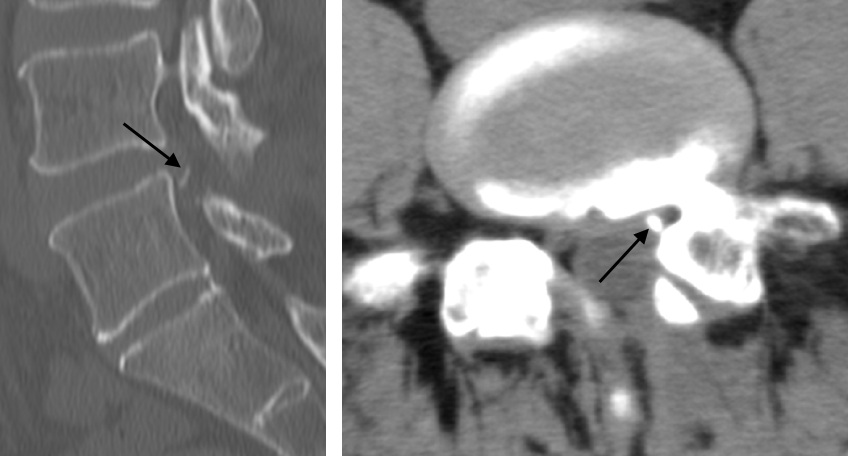

디스크 석회화는 척추의 디스크 내에서 칼슘이 비정상적으로 침착되는 상태를 의미합니다. 일반적으로 디스크는 외부의 섬유륜과 내부의 수핵으로 구성되어 있으며, 이들 구조는 척추의 충격을 흡수하고 안정성을 제공합니다. 그러나 다양한 원인으로 인해 디스크가 손상되거나 퇴행성 변화를 겪을 경우, 수핵이 섬유륜을 통해 밀려나게 되고, 이 과정에서 염증이 발생할 수 있습니다. 이러한 염증 반응은 칼슘 침착을 유도하여 디스크 석회화를 초래합니다.

디스크 석회화는 노화에 따른 퇴행성 변화, 외상, 유전적 요인 등 다양한 원인으로 발생할 수 있습니다. 디스크의 중심부인 수핵이 섬유륜을 통해 밀려나오는 현상을 디스크 돌출이라고 합니다. 이 과정에서 염증이 발생하고, 칼슘이 침착되어 디스크 석회화가 일어납니다. 이러한 석회화는 오랜 시간에 걸쳐 형성되므로 허리디스크를 장기간 앓고 있는 환자에게 주로 나타납니다. 또한, 디스크 제거 수술 후에도 염증이 생길 수 있으므로 적절한 관리가 필수적입니다.

CT 스캔을 통해 석회화된 부위를 확인할 수 있습니다. 허리 통증으로 병원을 방문하면 MRI 촬영이 일반적이지만, CT 촬영도 함께 진행하는 것이 좋습니다.